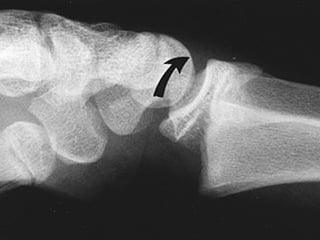

LOCALIZACION Diafisiaria Metafisiaria Epifisiaria Intraarticular Fractura-luxación

LOCALIZACION Diafisiaria MetafisiariaEpifisiaria Intraarticular Fractura-luxación